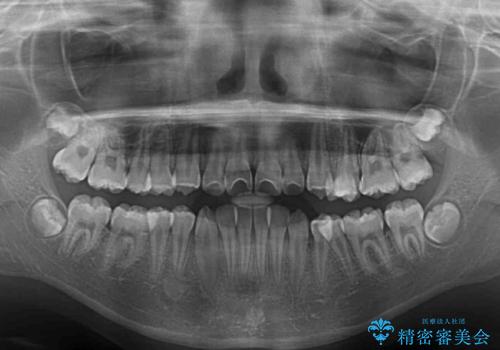

- 急速拡大装置・インビザライン

- 小児矯正の頃から診察を行っている患者様です。

上顎骨の幅が下顎骨よりも小さいので、拡大装置により骨幅を広げて上下関係を改善し、その後インビザラインにて歯並びを整えることとしました。

上下の骨幅を改善したことで、スムーズに歯列矯正を行うことができました。